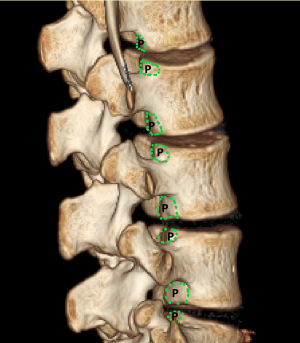

To investigate fully radiographic anatomy of PETOFPC, the authors chose to measure the distances from the posterior corner (P point, Figure 1) in lumbar spine to the corresponding targets.

Posterior corner in lumbar spine was selected as the screw entry point (P point) for oblique fixation. The screw entry point (P point) in posterior-inferior corner is the bony area between the upper margin of the pedicle and the upper endplate. The screw entry point (P point) in posterior-superior corner is the bony area between the lower margin of the pedicle and the lower endplate (Figure 2). The corresponding targets are A, B, C, D, E, and F, respectively (A: the middle point of the contralateral anterior-middle 1/3, B: the contralateral anterior-middle point, C: the middle point of the contralateral side, D: the upper point of contralateral anterior-middle 1/3, E: the contralateral anterior-upper point, F: the middle-upper point of the contralateral side) in the contralateral anterior region (Figure 3).